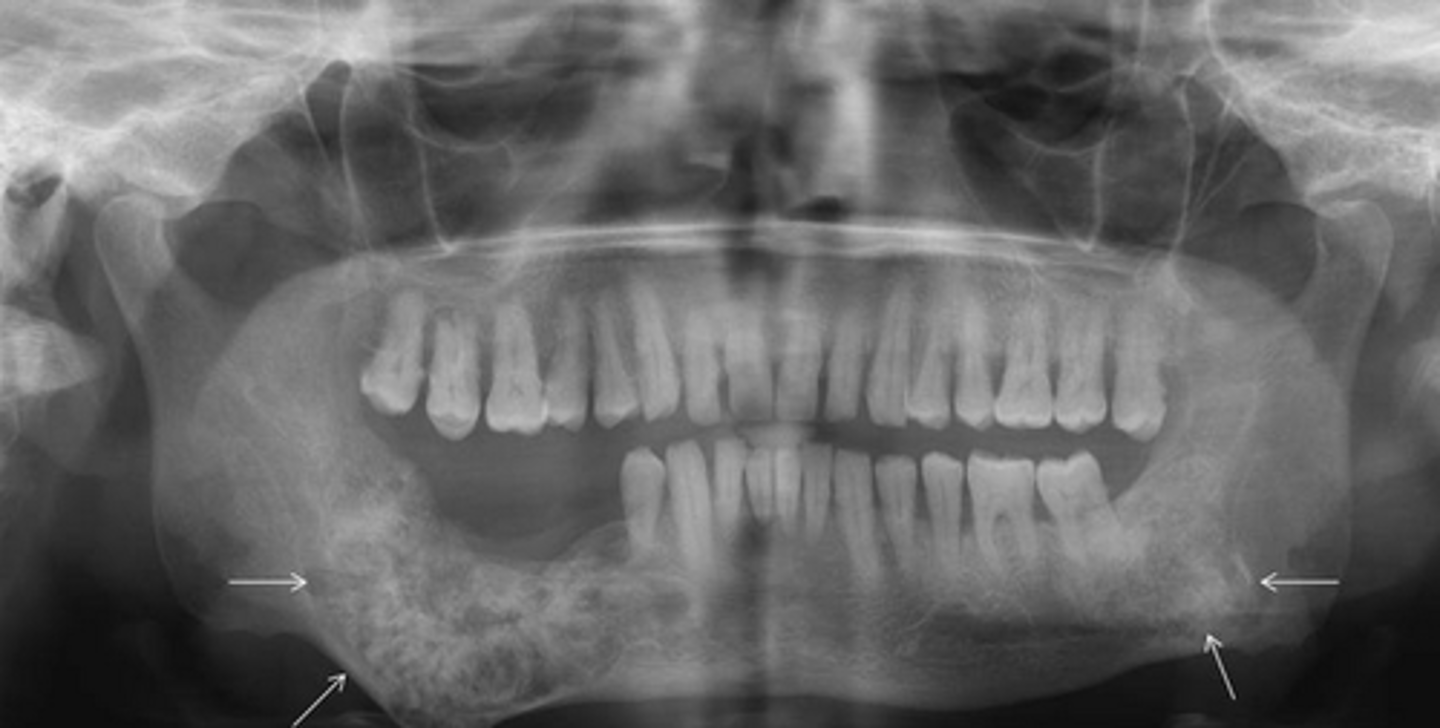

Diffuse sclerosing is seen in which condition?

Florid Osseous Dysplasia

What happens to the inferior border of the mandible in diffuse sclerosing?

Thinned

What is proliferative periostitis also known as?

Garre's Osteomyelitis

What is a characteristic appearance of Garre's Osteomyelitis?

Onion skin

Who is more affected by Garre's Osteomyelitis?

Females, younger